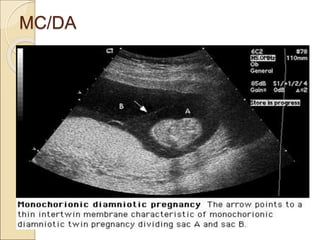

MC/DA

Chorionicity can be determined several

ways:-

 If separate placentas = DC/DA

 “Twin peak" or "lambda" = DC/DA

 Discordant genders = DC/DA

 Intertwin membrane thickness